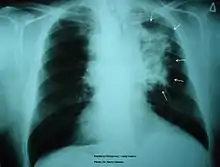

The morbidity of cigarette smoking is nearly 50% with 7 million first-hand smokers and 1.2 millions second hand smokers killed each year[8]. Regardless of active or passive smokers, macrophage accumulation is found in the lungs.[3][5] The diagnostic methods for smoke-related diseases include bronchoalveolar lavage which can also be used for examining smoker's macrophages in addition to augmented inflammatory cells in the alveolar lumen.[1]

The immune functions in smoker’s macrophages are compromised, so the airway pathogens are more likely to accumulate and cause infection.[17] Smoker’s macrophages have reduced expression of HLA-DR antigens, causing immunosuppression.[18][19] In addition, nicotine impairs the phagocytosis of M. tuberculosis and also induces immunosuppression via the activation of alpha-7 nicotinic receptors.[4][17] Meanwhile, due to the impaired TLR2 and TLR4 signaling, macrophages fail to recognize pathogens, so there is a decrease in pathogen clearance.[17] Therefore, smokers are prone to acute respiratory tract infection and community acquired pneumonia.[20]

Smoking is found to be the most important causative factor leading to COPD.[23] Because of the altered inflammatory response of the macrophages, smoking induces inflammation across the entire airway, which in turns obstructs the airflow. Symptoms of COPD include persistent coughing, wheezing, chest infections and breathlessness. Treatments for COPD usually focus on the source of the problem, which is smoking, thus the general treatment is going through smoking rehabilitation which including nicotine replacement therapy, mental therapy for advice, and support to quit smoking. In certain urgent cases, direct constriction also occurs, in which bronchodilators allow the airway to dilate.